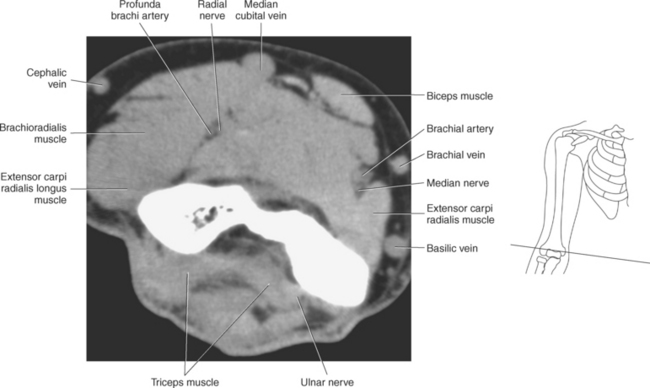

The primary arteries supplying the shoulder region include the axillary and brachial arteries (Figures 9.34 through 9.45 and 9.144, A). The axillary artery begins at the lateral border of the first rib as a continuation of the subclavian artery. It ends at the inferior border of the teres major muscle, where it passes into the arm and becomes the brachial artery. The axillary artery and its branches supply blood to numerous thoracic and shoulder structures, including the first and second intercostal spaces, axillary lymph nodes, mammary gland in women, and scapular, serratus anterior, pectoral, latissimus dorsi, deltoid, and triceps brachii muscles. The branches of the axillary artery typically include the superior thoracic, thoracoacromial, lateral thoracic, subscapular artery, and anterior and posterior humeral circumflex arteries. The brachial artery is the principal arterial supply to the arm. It courses inferiorly on the medial side of the humerus then continues anterior to the cubital fossa of the elbow. The brachial artery is relatively superficial and palpable throughout its course. It accompanies the median nerve, which crosses anterior to the artery in the middle of the arm. During its course, the brachial artery gives rise to numerous muscular branches, which include the profunda brachii, superior ulnar collateral, and inferior ulnar collateral arteries (Figure 9.144, A).

The veins of the upper arm include the brachial, cephalic, and basilic (Figure 9.146). The two deep brachial veins ascend the arm, one on either side of the brachial artery. The brachial veins begin in the elbow from the union of the ulnar and radial veins and end in the axillary vein near the lower margin of the subscapularis muscle. The two deep brachial veins may join to form one brachial vein during part of their course. The superficial veins of the upper arm include the cephalic and basilic. The cephalic vein courses from the radial side of the dorsal venous arch of the hand and then ascends to the midpoint of the forearm, where it curves around to the ventral surface of the forearm and ascends the lateral aspect of the upper arm, along the anterolateral border of the biceps brachii muscle, to open into the axillary vein, just below the clavicle. It drains the superficial parts of the lateral hand and lateral forearm. The basilic vein originates from the medial end of the dorsal venous arch of the hand. It then ascends the ulnar side of the forearm, along the medial surface of the biceps brachii muscle, in the upper arm, to form the axillary vein. The basilic vein drains the superficial parts of the medial side of the hand and medial side of the forearm. The large axillary vein lies on the medial side of the axillary artery. It extends from the lower border of the teres major muscle to the lateral surface of the first rib to continue as the subclavian vein. The axillary vein receives tributaries that correspond to the branches of the axillary artery (Figures 9.34 through 9.47).

The large deep vein of the elbow is the brachial vein, which is formed by the union of the radial and ulnar veins. The superficial veins of the elbow include the cephalic, median cubital, basilica, and intermediate (median) antebrachial veins. The cephalic vein courses along the radial side of the elbow and may give rise to the median cubital vein, which ascends in an oblique and medial course to create an anastomosis between the basilic and cephalic veins (Figure 9.145). The median cubital vein is a common site for venipuncture. The basilic vein courses along the posteromedial aspect of the forearm, crosses the elbow, then takes a deep course in the axilla to joint the brachial vein. The intermediate (median) antebrachial vein transports blood from the superficial palmar venous arch and anterior forearm. It ascends the ventral side of the forearm on the ulnar side and typically ends in the basilic vein (Figures 9.147, 9.60 through 9.67, and 9.87 through 9.98).